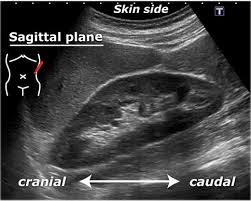

Kidney scan results your scan will go to a radiologist or other doctor trained to read the images. A gfr of 60 or higher is in the normal range. Ensure the kidney is thoroughly examined from edge to edge.

Ensure the kidney is thoroughly examined from edge to edge. We will explain everything that we see on scan and give you a clinical report of our findings and we can send them to your doctor or healthcare provider. A kidney ultrasound may be performed to assist in placement of needles used to biopsy obtain a tissue sample the kidneys to drain fluid from a cyst or abscess or to place a drainage tube. If you want to know the results of your blood tests please ask your doctor to explain them.